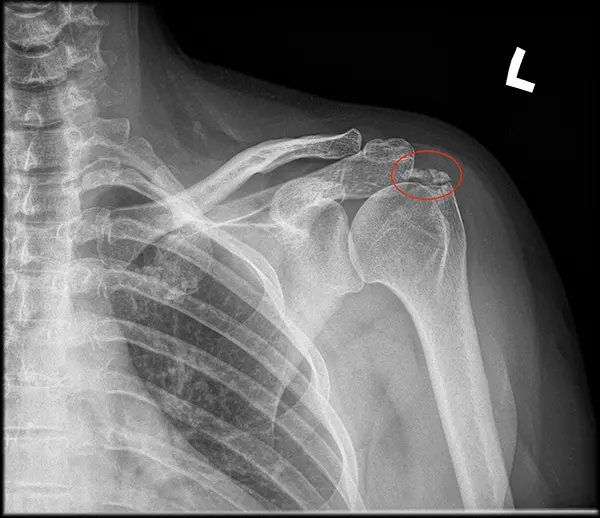

Wapniejące zapalenie ścięgna stożka rotatorów

Wapniejące zapalenie ścięgna stożka rotatorów to schorzenie, które charakteryzuje się obecnością zwapnień zbudowanych z kryształów hydroksyapatytu w obrębie ścięgna. Chociaż dokładne pochodzenie tych zwapnień pozostaje nieznane i może mieć podłoże genetyczne, to schorzenie to może wywoływać różnorodne objawy. Poniżej przedstawiam bardziej szczegółowy opis tego stanu oraz dostępne metody diagnozowania i leczenia.

Zwapnienia w obrębie mankietu rotatorów mogą przybierać różne formy, takie jak dobrze zdefiniowane, zaokrąglone (typ A), wielopłatowe (typ B) lub o niewyraźnych, mętnych granicach (typ C). Ważne jest, aby nie mylić ich z mikrozwapnieniami, które stanowią część entezopatii zwapnieniowej, wskazującej na bardziej klasyczne zapalenie ścięgna bez obecności zwapnień.